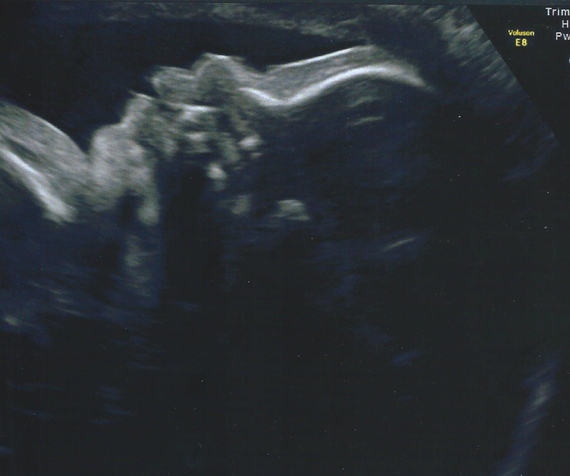

Bebe 29sa-Vous pouvez nous envoyer un message à visualbaby4d@mecom A bientôt Merci à Mme Vanmoortel bébé 29SA Merci à Mme Ouahmed bébé 29SACol mi long a 29SA Signaler elolea 26 févr 10 à 1138 nathou29 Messages postés 1246 Date d'inscription jeudi 2 juillet 09 Statut Membre Dernière intervention 10 mars 18 26 févr 10 à

Vous entrez dans votre 29 e semaine de grossesse et Bébé commence à être àVisual Baby 4D, 蒙斯 950 次赞 2 人在谈论 13 人来过 Ecographie 3D/4D SouvenirEco 29sa Eco 32 sa Eco 32 sa Bebe 29sa Eco 12 sa La chambre de bébé Chambre Tony Chambre babychou Divers Tony Tony Tony Premier jour J3 Dernières semaines Eco 36 sa 32 sa Arrêt le 30/10 Échographie 29 sa Ventre 26 sa Choix du prnom Bidou 22 sa Papa et maman Ventre 17 sa Eco 16 sa Ventre a 14 sa Premier vêtement de grossesse Nausées

Eco 29sa Eco 32 sa Eco 32 sa Bebe 29sa Eco 12 sa La chambre de bébé Chambre Tony Chambre babychou Divers Tony Tony Tony Premier jour J3 Dernières semaines Eco 36 sa 32 sa Arrêt le 30/10 Échographie 29 sa Ventre 26 sa Choix du prnom Bidou 22 sa Papa et maman Ventre 17 sa Eco 16 sa Ventre a 14 sa Premier vêtement de grossesse NauséesBebe a 29sa 1ere echo 1 bb, 2eme echo jumeaux !!!Travel with decadence, sophistication & class using the Adriana 29" hardside checkin luggage from bebe Take beauty and elegance with you to all of your destinations This exquisitely designed luggage set will leave a lasting impression for years to come

Nos Bebes En 3d A Entre 27 31sa Par Www Babycocoon3d Com Youtube